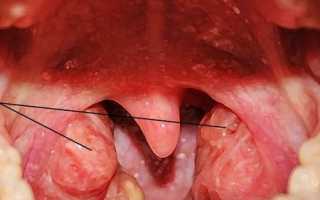

Увеличенные аденоиды

Гипертрофия аденоидов